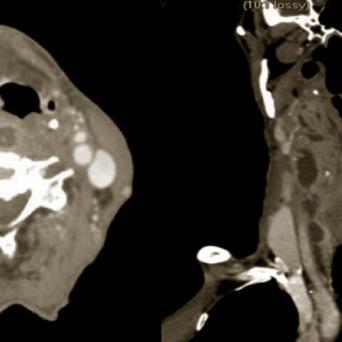

L’image

du jour

Illustration.